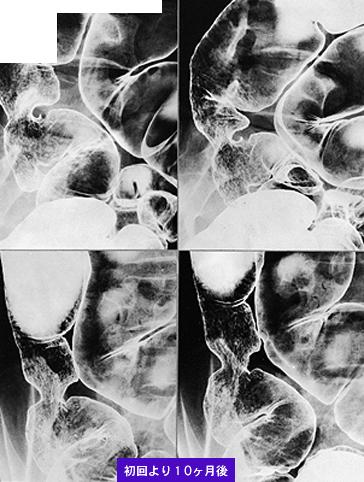

肠结核

采用抗结核药物几乎治愈的由于不明原因出血而实行切除的大肠结核疑似病例

[ Image ID:9108 ]

炎症性・溃疡性疾患/结核

部位(按器官分)

大肠/占据大肠的2个以上区域

检查方法

X线